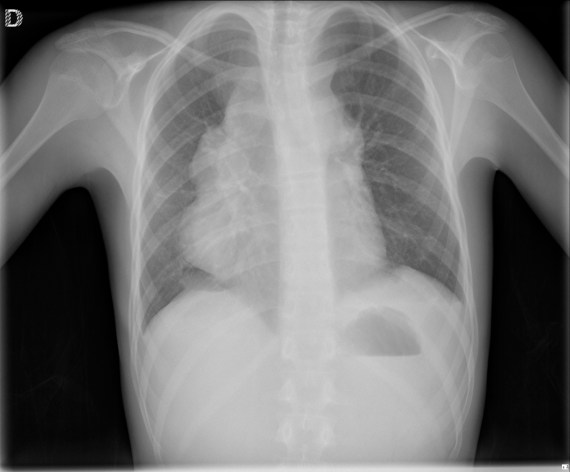

CASO: Febrícula y tos de 4 días de evolución.

Hallazgos:

- En la placa PA se observa una asimetría en los hilios pulmonares, el hilio izquierdo tiene una densidad aumentada.

- Tras examinar la placa lateral se observa un aumento de densidad en la columna que puede ser compatible con una condensación, es el signo de la desnificación vertebral.

SIGNO DE LA DENSIFICACIÓN VERTEBRAL: En la radiografía lateral normal, la densidad de la columna torácica tiende a disminuir desde la parte superior hasta el diafragma; la alteración de ese patrón por la presencia de una densidad superpuesta a la columna, indica la existencia de una consolidación pulmonar. Este signo adquiere especial valor cuando en la proyección posteroanterior la consolidación está oculta en el espacio retrocardíaco o en la base pulmonar.